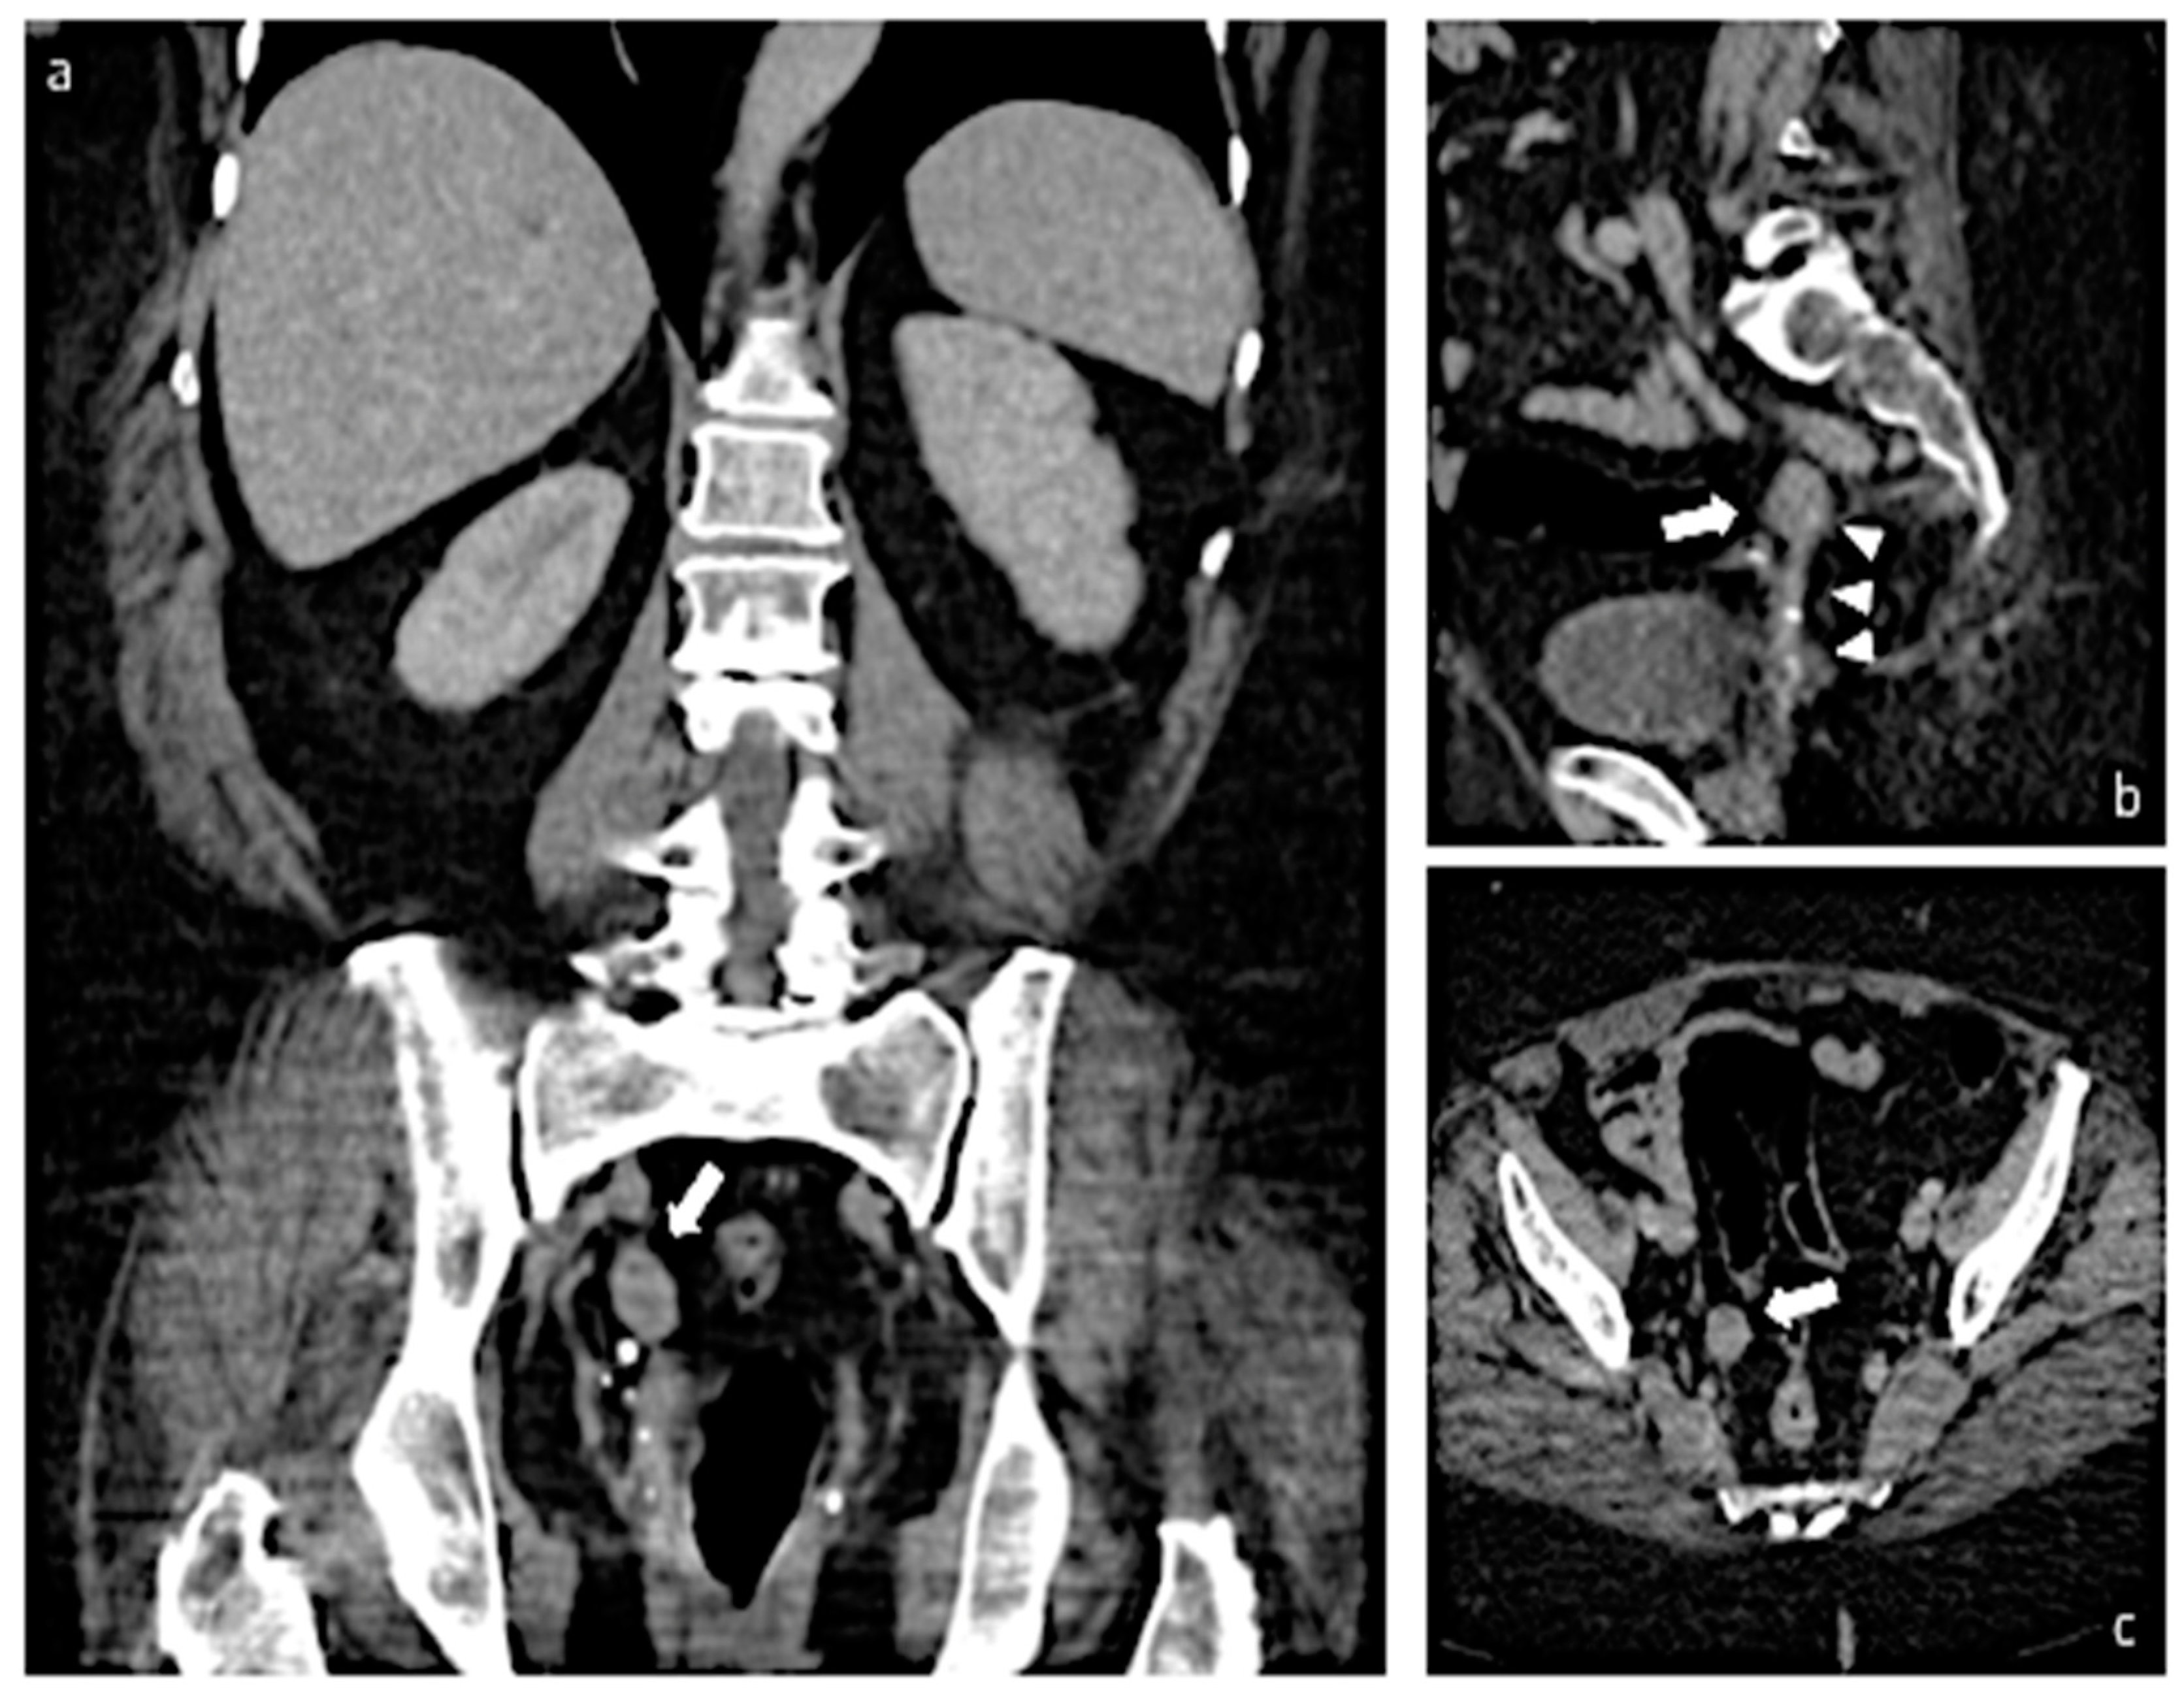

2. Case Report